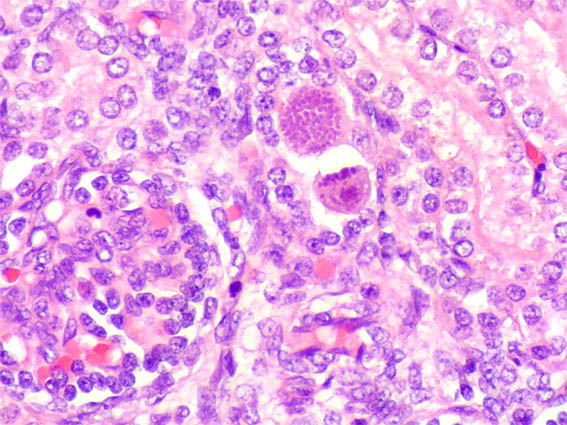

En ambos riñones fetales se observa lo mostrado en las siguientes imágenes.

Figura 3.

H&E, X400.